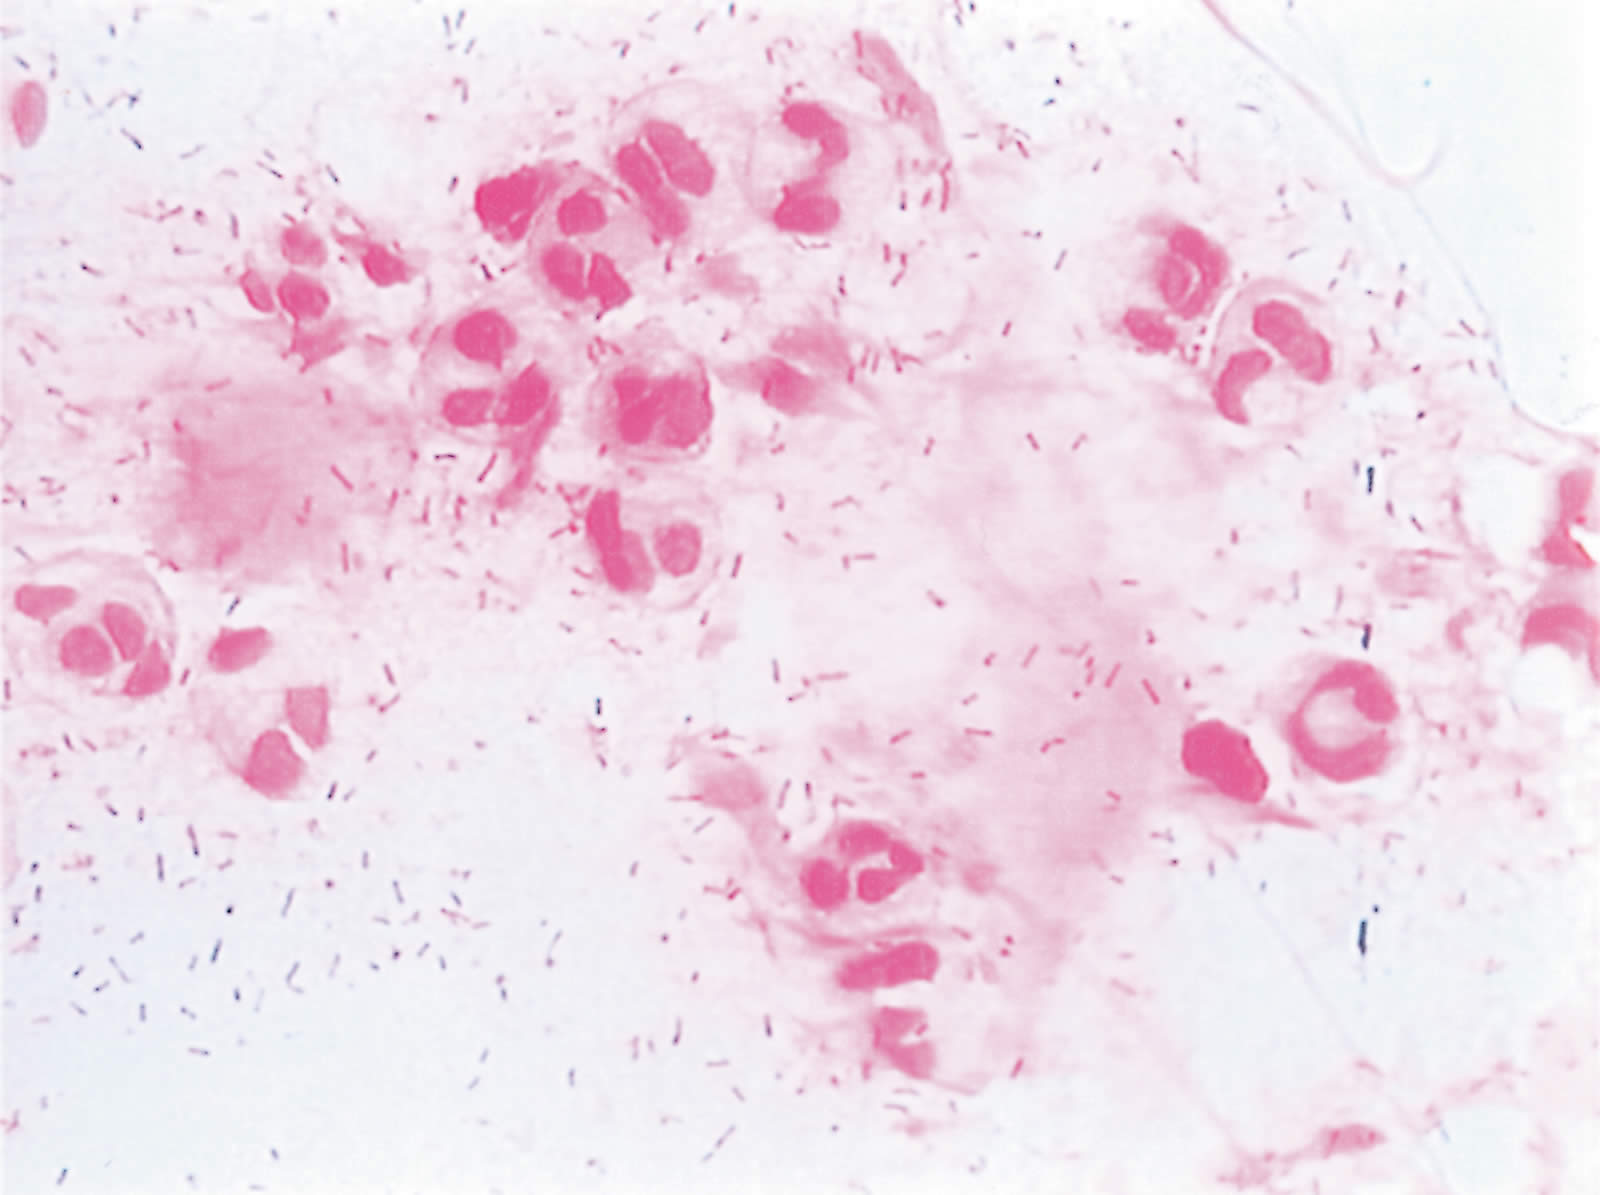

Bacterial conjunctivitis

Symptoms and signs: red eyes, discharge of pus, pain.

It is usually bilateral. It may start in one eye and later spread to the other.

The common organisms are the Staphylococcus aureus, Staphylococcus epidermidis, Group A Streptococcus and Streptococcus pneumoniae. Other organisms are Haemophilus influenzae, Pseudomonas and Escherichia coli.1 Moraxella lacunata causes an angular conjunctivitis with a whitish discharge at the outer canthus. The spectrum of organisms causing conjunctivitis varies around the world.